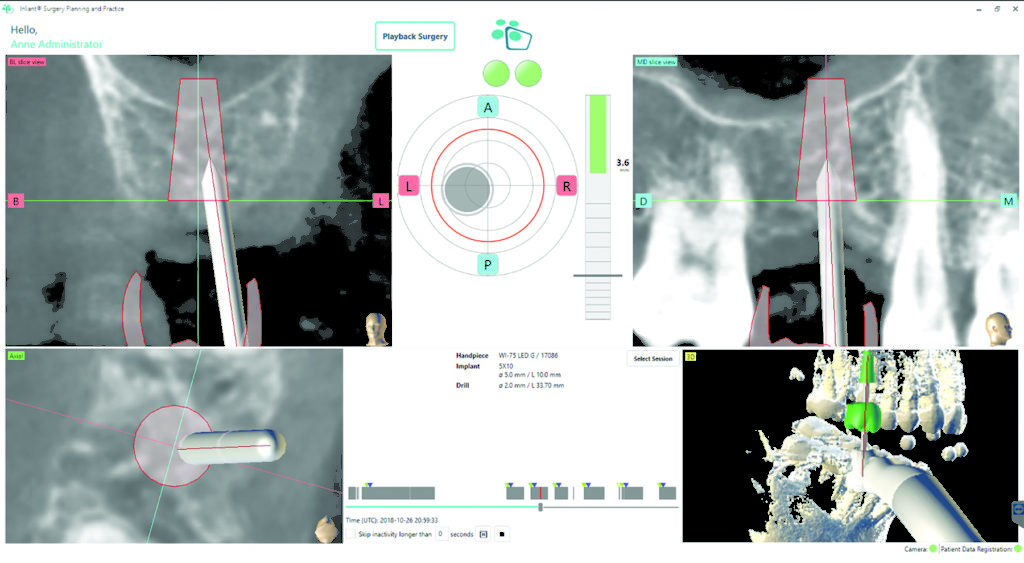

:sharpen(level=0):output(format=jpeg)/up/dt/2018/03/MVIMG_20180201_082138.jpg)